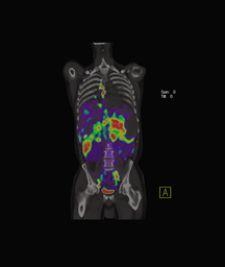

PET/CT in molecular imaging takes a 'photograph' of biological targets or pathways in the body for 'personalized medicine.' Photo courtesy of Siemens.

Over the next 10 years, the hybrid PET/CT modality is expected to surpass dedicated PET devices in terms of adoption, as the combined functional and anatomical information produced by the hybrid has proven increasingly beneficial in oncology and cardiology. PET/CT will also play an important role in the future of molecular imaging, which aims to “photograph” biological targets or pathways in the body for “personalized medicine,” which will eventually provide patient-specific information that allows clinicians to tailor the treatment of disease. These developments have charged the leading PET/CT manufacturers, GE Healthcare, Siemens, Hitachi and Philips, with enhancing image quality in the hybrid – particularly in PET. What is intriguing is that each manufacturer is approaching this challenge in its own way.